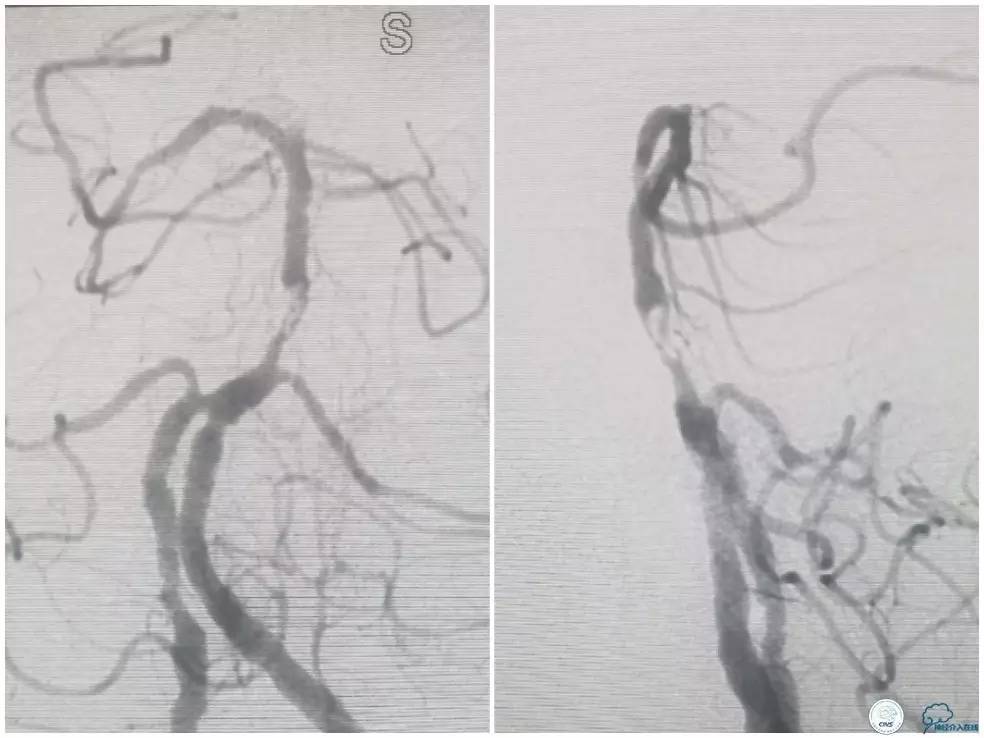

颅内动脉粥样硬化性狭窄多为偏心性狭窄分布于管腔某一壁。但我们也可见突出于管腔内的狭窄,造影显示狭窄轮廓不清,某些投造体位可见充盈缺损(图1,来自秦皇岛市第一医院,杨大为主任提供),类似“蜂巢样”改变,或者呈“夹层样”改变。本周我们汇报病例系一例基底动脉“蜂巢样”狭窄支架治疗的过程。

图1